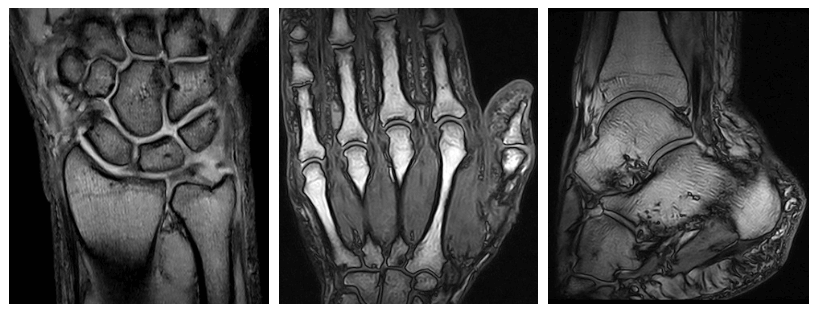

L'apparecchiatura impiegata permette di produrre immagini ad alta risoluzione, non produce interazioni negative con i. La risonanza magnetica è una metodica diagnostica non invasiva che utilizza radiazioni elettromagnetiche totalmente innocue per l'organismo. La risonanza magnetica, sia essa aperta o chiusa, non è un esame doloroso.

Diversamente dalla classica risonanza magnetica ad alto campo generalmente la risonanza magnetica aperta è richiesta dai genitori i cui bambini necessitano di essere sottoposto ad un esame di risonanza. Infatti l'ampio spazio disponibile, compreso fra il lettino dove si trova il paziente e la piastra sovrastante, unitamente al campo magnetico di 1 tesla. La risonanza magnetica è una metodica diagnostica non invasiva che utilizza radiazioni elettromagnetiche totalmente innocue per l'organismo.